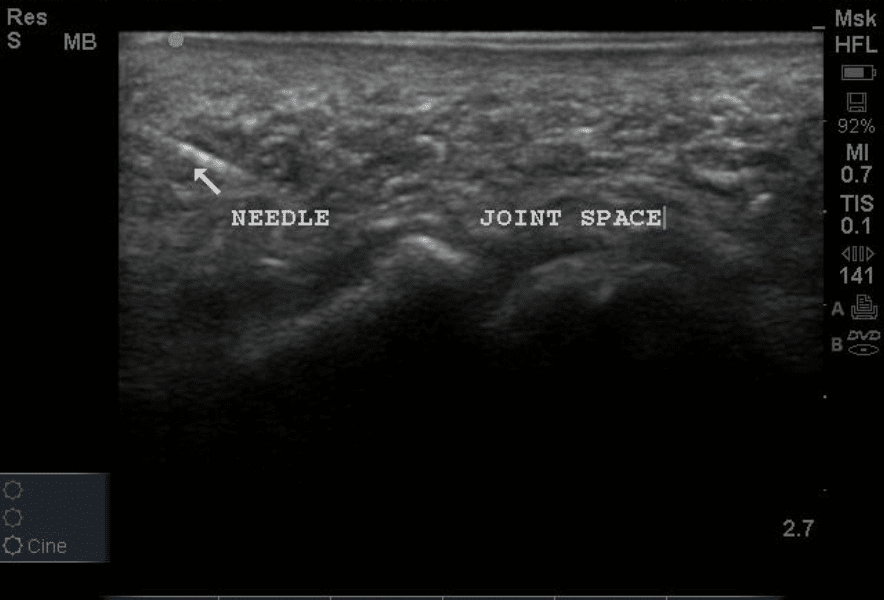

Dr. Jonathan Watson, an emergency department physician at a leading hospital in Atlanta, used the Dr. Sono Tri-Scan Max with a linear probe to locate a broken needle embedded in a patient’s foot. Despite a thorough wound cleaning, evaluation, and X-ray imaging, the foreign body (FB) was not immediately visible, prompting further investigation with the ultrasound.

Utilizing Dr. Sono’s high-frequency linear probe, Dr. Watson was able to pinpoint the exact location of the broken needle, which had been missed on the X-ray due to its radiolucent properties. The ultrasound scan provided a clear, real-time view of the needle's position within the soft tissue, enabling precise measurement of its depth and proximity to the skin surface. Thanks to Dr. Sono, Dr. Watson was able to make a small incision directly over the needle and remove it with minimal discomfort to the patient.